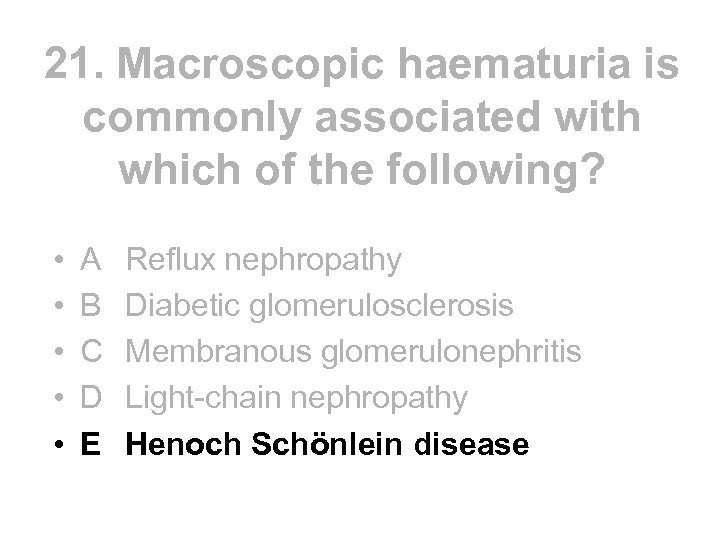

21. Macroscopic haematuria is commonly associated with which of the following? • • • A B C D E Reflux nephropathy Diabetic glomerulosclerosis Membranous glomerulonephritis Light-chain nephropathy Henoch Schönlein disease

21. Macroscopic haematuria is commonly associated with which of the following? • • • A B C D E Reflux nephropathy Diabetic glomerulosclerosis Membranous glomerulonephritis Light-chain nephropathy Henoch Schönlein disease

21. Macroscopic haematuria is commonly associated with which of the following? • • • A B C D E Reflux nephropathy Diabetic glomerulosclerosis Membranous glomerulonephritis Light-chain nephropathy Henoch Schönlein disease

21. Macroscopic haematuria is commonly associated with which of the following? • • • A B C D E Reflux nephropathy Diabetic glomerulosclerosis Membranous glomerulonephritis Light-chain nephropathy Henoch Schönlein disease

Common causes Haematuria Urological • Cancers of kidney, bladder or prostate • Stones • Urinary infection • Benign tumours eg bladder papilloma • Trauma Nephrological • Ig. A nephropathy • Henoch Schonlein Purpura • Alports Syndrome • Other glomerular disease (usually with proteinuria) • Polycystic kidney • Medullary sponge

Common causes Haematuria Urological • Cancers of kidney, bladder or prostate • Stones • Urinary infection • Benign tumours eg bladder papilloma • Trauma Nephrological • Ig. A nephropathy • Henoch Schonlein Purpura • Alports Syndrome • Other glomerular disease (usually with proteinuria) • Polycystic kidney • Medullary sponge